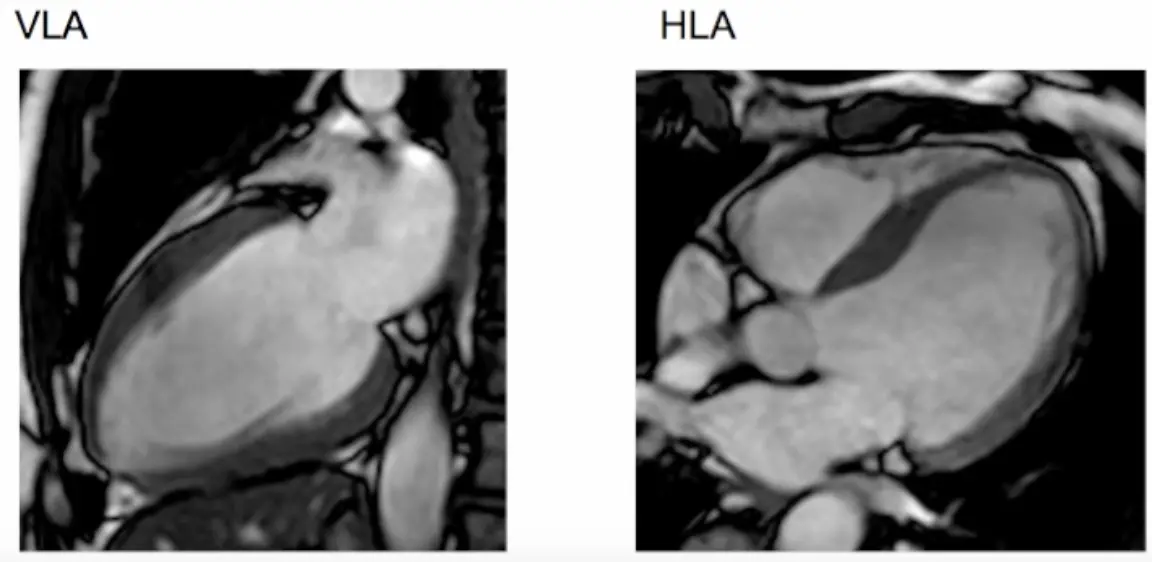

- Step 1. Scouts and planning views (VLA, HLA)

- Next we slice the resulting VLA view: again, we cut across the apex and the middle of the mitral valve (where the two leaflets meet) → results in a horizontal LAX (HLA) view

- Resulting scout views include VLA and HLA views